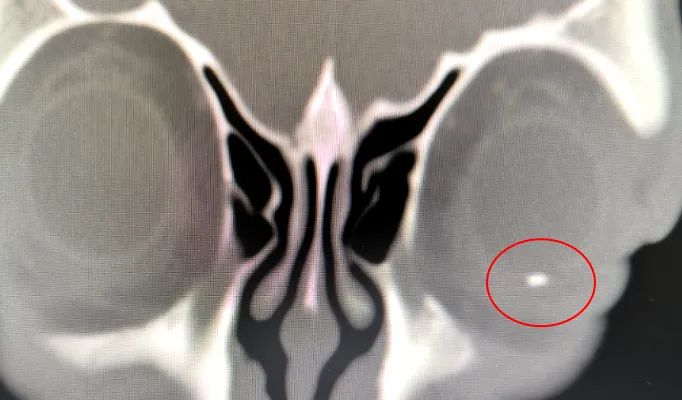

眼科耳鼻咽喉科主任、副主任医师胡习莲为甘大叔作了详细检查。经眼部CT、眼部B超检查,发现甘大叔眼球里竟存在一大小约4mm的异物。

眼部CT图像

这枚异物已经造成甘大叔左眼晶状体形态异常、全眼球炎症。若不处理该异物,该异物将作为一枚“不定时炸弹”,反复诱发眼内炎症,导致患者痛苦加重,甚至摘除眼球。综合考虑下,胡习莲主任决定为甘大叔进行手术,将异物取出。

术中,胡习莲主任自患者左眼角膜开始,层层递进,依次打开粘连的虹膜、摘除已液化的晶状体、切除浑浊的玻璃体,最终在患者视网膜6点钟位置近赤道部,发现了这枚“炸弹”。